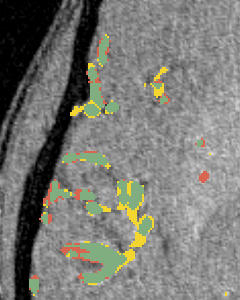

3.3 Segmentation around Bifurcation Points (BPs)

(a)

(b)

(c)

(d)

(e)

In this experiment, we demonstrate the importance of our predicted bifurcation flow fields () in vessel-segmentation performance around BPs. To quantitatively measure the segmentation, we manually annotated bounding boxes (BBs) at multiple bifurcation regions in the DRIVE dataset. We performed an ablation study, where we didn’t consider bifurcation loss (BL) in our final formulation. Figure 2(c) reports the accuracy of identifying vessel pixels within the extracted BBs. Our proposed bifurcation loss significantly improves the segmentation at regions around BPs.